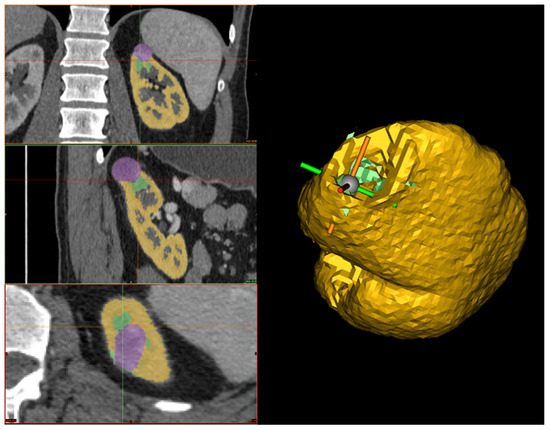

Reconstruction refinement. Since the organ and the tumor are reconstructed independently, it is essential to check for pairwise inconsistencies. These could involve irregularities in the kidney’s boundary, holes in the kidney interface with the tumor, overlapping, or a lack of contact between the two.

Therefore, the first step in correcting the reconstruction is to remove any tumor parts mistakenly considered part of the organ during kidney segmentation. Then, the human operator should inspect the interface between the tumor and the kidney to confirm the absence of gaps. If any holes are present, the Fill command is used to address them while checking each slice across the three sections (see Figure 6). Finally, before exporting the 3D models, a smoothing operator is applied to slightly refine the geometries of the two volumes. The final result can be seen in Figure 1, which was obtained from a combination of automated and manual tumor and organ segmentation. As previously discussed, organ and tumor segmentation is fundamental for the algorithm presented in Section 2.2. Here, we described a manual procedure for this segmentation. However, in the future, this could be replaced with a fully automated process.

Figure 6. On the left, the hole-filling process across the three different planes is shown, where the purple represents the tumor, the yellow represents the kidney, and the green indicates the manually filled region used to close the gap between the tumor and the kidney. On the right, the 3D reconstruction of the kidney after the filling process is displayed, where the yellow represents the kidney, and the green corresponds to the filled part of the kidney.